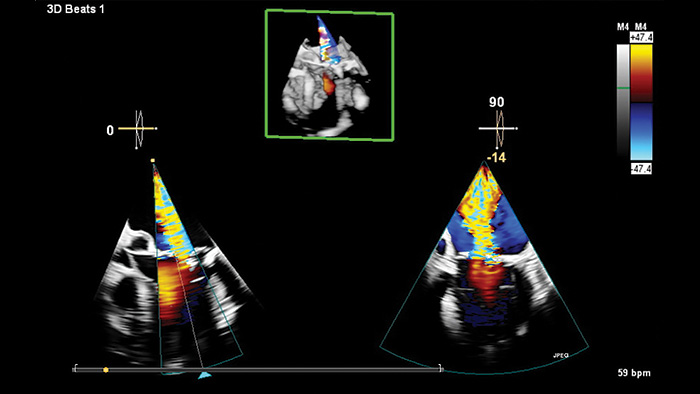

O Transcend Plus melhora visivelmente a nitidez, o contraste e os detalhes em imagens 2D e 3D, apresentando os mais recentes aprimoramentos aprovados pela FDA para EPIQ CVx e Affiniti CVx. Essas atualizações oferecem suporte superior à visualização da anatomia e função cardíacas, permitindo confiança no diagnóstico mesmo nos casos mais complexos ou tecnicamente desafiadores. A atualização também apresenta o novo recurso 2D Auto EF Advanced, expandindo os recursos de IA para imagens de contraste - essenciais para avaliar com precisão a função cardíaca.

A Philips agora oferece 26 aplicativos de IA de ultrassom cardiovascular aprovados pela FDA - o maior número do setor - totalmente integrados ao Transcend Plus para os sistemas EPIQ e Affiniti CVx. Entre os aprimoramentos mais recentes a receber a autorização da FDA 510(k) estão o 2D Auto EF e o 2D Auto EF Advanced. Essas ferramentas avançadas são projetadas para simplificar os fluxos de trabalho clínicos e melhorar a precisão do diagnóstico em uma variedade de ambientes de atendimento, desde o laboratório de ecocardiografia até o hospital e clínicas ambulatoriais, pré-avaliação e acompanhamento de longo prazo. Com esses aplicativos integrados de IA, os médicos podem avaliar os pacientes de forma mais rápida, consistente e confiante em todo o continuum de atendimento.

A avaliação da função ventricular esquerda (VE) é uma das aplicações mais críticas em imagens cardíacas, desempenhando um papel central no diagnóstico e gerenciamento de uma ampla gama de condições cardíacas. O Transcend Plus atende diretamente a essa necessidade, fornecendo resultados rápidos e reprodutíveis que ajudam os cardiologistas a avaliar rápida e definitivamente a função do VE de forma consistente em diferentes pacientes e ao longo do tempo. As ferramentas automatizadas minimizam a variabilidade do operador, garantindo medições mais confiáveis e padronizadas, especialmente vitais em ambientes clínicos de alto volume ou alta pressão. Além disso, o Transcend Plus oferece suporte robusto para imagens com e sem contraste. O recurso 2D Auto EF permite avaliações precisas mesmo quando os agentes de contraste não podem ser usados, como em pacientes com insuficiência renal. Com base nisso, o 2D Auto EF Advanced adiciona recursos de quantificação alimentados por IA para estudos de contraste e sem contraste, ampliando a aplicabilidade clínica e aumentando a confiabilidade da medição em pacientes com baixa qualidade de imagem ou janelas acústicas desafiadoras. Esses recursos se combinam para oferecer uma abordagem mais confiante e eficiente para o atendimento cardíaco.